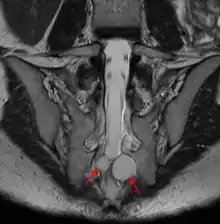

MRI image showing a Tarlov cyst

MRI, or Magnetic Resonance Imaging, is considered the imaging study of choice in identifying Tarlov cysts. MRI provides better resolution of tissue density, absence of bone interference, multiplanar capabilities, and is noninvasive. Plain films may show bony erosion of the spinal canal or of the sacral foramina. On MRI pictures, the signal is the same as the CSF one.